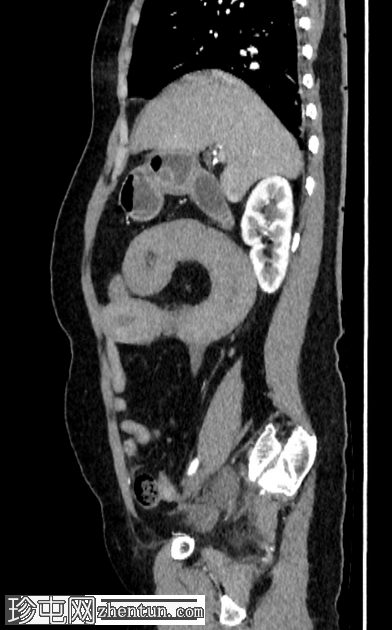

轴位

非增强

肠壁强化减弱,高度提示肠缺血。

腹腔内可见中等量腹水。

低灌注综合征:

血管表现

腹主动脉管径变细:前后径12 mm

腹主动脉分支变细:腹腔干5.3 mm;肝总动脉3.2 mm;脾动脉1.5 mm;肠系膜动脉直径 4.4 mm

下腔静脉扁平征

内脏表现

脾脏灌注不足,脾脏体积略有缩小:初始测量值为 57 x 35 x 38 mm,后续影像学检查缩小至 56 x 31 x 33 mm

肝脏灌注不足:肝实质呈不均匀强化,主要累及右肝叶

双侧肾上腺强化

双侧可见肾图增高、延长且呈条纹状

影像学表现提示自发性空肠壁内出血,伴有肠壁缺血的证据,导致出血性休克和弥漫性血管痉挛。CT 扫描期间,患者正在接受血管加压药物支持。

红细胞计数:1,77。血红蛋白:54 克/升。红细胞压积:16.4%。

国际标准化比值:28.3。